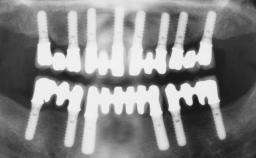

Rehabilitating an Edentulous Maxilla with a Fixed Dental Prosthesis Following Provisional Immediate Loading

This case features the flapless computer-guided placement of 7 bone-level implants, distributed to provide maximal support for the prosthetic framework. A rigid one-piece metallic framework was utilized as an interim restoration to reduce the risk of fracture associated with this prosthetic design. As part of the clinical examination, the SAC Assessment Tool was used, resulting in a surgical and restorative risk classification as “complex”.

Case Type Edentulous Maxilla

# of Implants 7

Type of Implants Two-Piece

Guided Surgery Yes

Prosthesis Type FDP